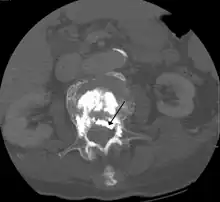

A CT image of cement used in kyphoplasty that has entered the spinal channel and is pressing on the spinal cord resulting in neurological symptoms

Some of the associated risks are from the leak of acrylic cement to outside of the vertebral body. Although severe complications are extremely rare, infection, bleeding, numbness, tingling, headache, and paralysis may ensue because of misplacement of the needle or cement. This particular risk is decreased by the use of X-ray or other radiological imaging to ensure proper placement of the cement.[2] In those who have fractures due to cancer, the risk of serious adverse events appears to be greater at 2%.[23]